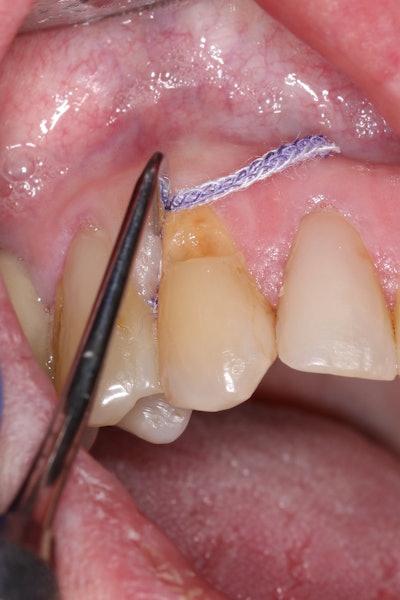

To improve isolation and soft-tissue access, a retraction cord was placed before initiating the procedure (Figure 2).

Figure 2: Placement of a retraction cord to improve isolation and access to the cervical area prior to preparation.Figure 2: Placement of a retraction cord to improve isolation and access to the cervical area prior to preparation.